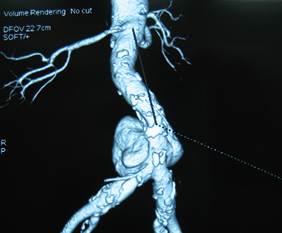

Thương tổn trên phim cắt lớp và/hoặc cộng hưởng từ

Hình dạng: Hình thoi: 7 bệnh nhân (26%). Hình túi: 20 bệnh nhân (74%).

Kích thước: Trung bình: 58.2 ± 21 mm. Lớn nhất: 100 mm. Nhỏ nhất: 20mm.

Hình 1: Phình động mạch chủ bụng hình túi trên CT Scanner